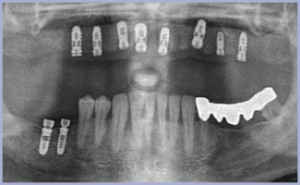

- Fig. 1 – OPT iniziale

- Fig. 4 – Opt a 4 mesi dall’intervento chirurgico di posizionamento implantare

- Fig. 12 – Follow-up radiografico a 12 mesi dal carico

- Fig. 13 – OPT a 4 mesi dall’intervento chirurgico

- Fig. 26 – Follow-up radiografico a 24 mesi dal carico